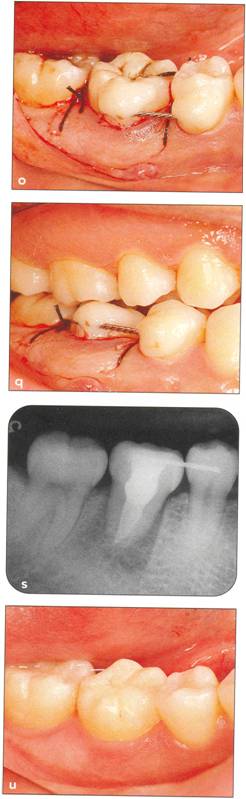

Fi 545e45f g 5-10 Stabilization of the donor tooth. The donor tooth has been splinted to the adjacent tooth with twisted wire and selfcured composite resin after etching and bonding. Fi 545e45f g 5-1 p After transplantation. |

Fi 545e45f g 5.1q Occlusal relationship after transplantation. The donor tooth is out of occlusion. Fi 545e45f g 5-1r Protection of the wound and prevention of infection by the use of surgical dressing. |

Fi 545e45f g 5-15 Three weeks after transplantation. Root canal therapy was started 2 weeks after transplantation. After temporary obturation with calcium hydroxide, the root canal was obturated with gutta percha in 5 weeks. Fi 545e45f g 5-1t Two and one half months after transplantation. |

Fi 545e45f g 5-1 u Definitive occlusal restoration of the donor tooth with composite resin. Fi 545e45f g 5-1v One year 3 months after transplantation. Normal periodontal ligament space and lamina dura are observed. |